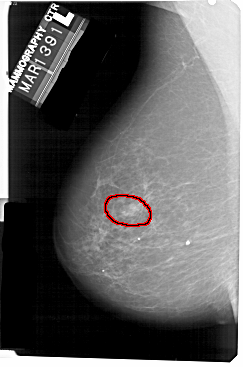

FILE: A_1341_1.LEFT_MLO.OVERLAY

TOTAL_ABNORMALITIES 1

ABNORMALITY 1

LESION_TYPE MASS SHAPE ROUND MARGINS ILL_DEFINED

ASSESSMENT 4

SUBTLETY 4

PATHOLOGY BENIGN

TOTAL_OUTLINES 1

BOUNDARY